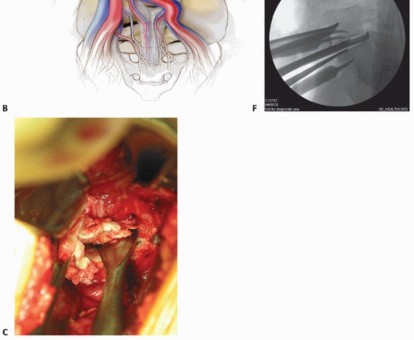

In cases of corpectomy for vascular tumors, preoperative embolization should be performed (TECH FIG 6A).

In cases of corpectomy, radical discectomies are performed above and below the vertebral body to be removed (see discectomy technique discussed earlier).

This enables the surgeon to become oriented to the midline and also to judge the depth and width of the corpectomy to be performed.

The discectomy space also allows the surgeon to use a large rongeur efficiently to remove the vertebral body (TECH FIG 6B).

- TECH FIG 6 • A. Preembolization angiogram depicting the aortic bifurcation in a 65-year-old patient with metastatic renal cell carcinoma to the L4 vertebra. Note the degree of vascularity of the L4 vertebral body.

- B. Postembolization angiogram depicting a striking reduction in contrast entering the L4 vertebral body. Small embolization coils are seen in the vascular network surrounding the vertebral body. C. Anterior discectomy enables the surgeon to use a large rongeur to gain access to the edge of the vertebra and thereby remove the vertebral body bone.